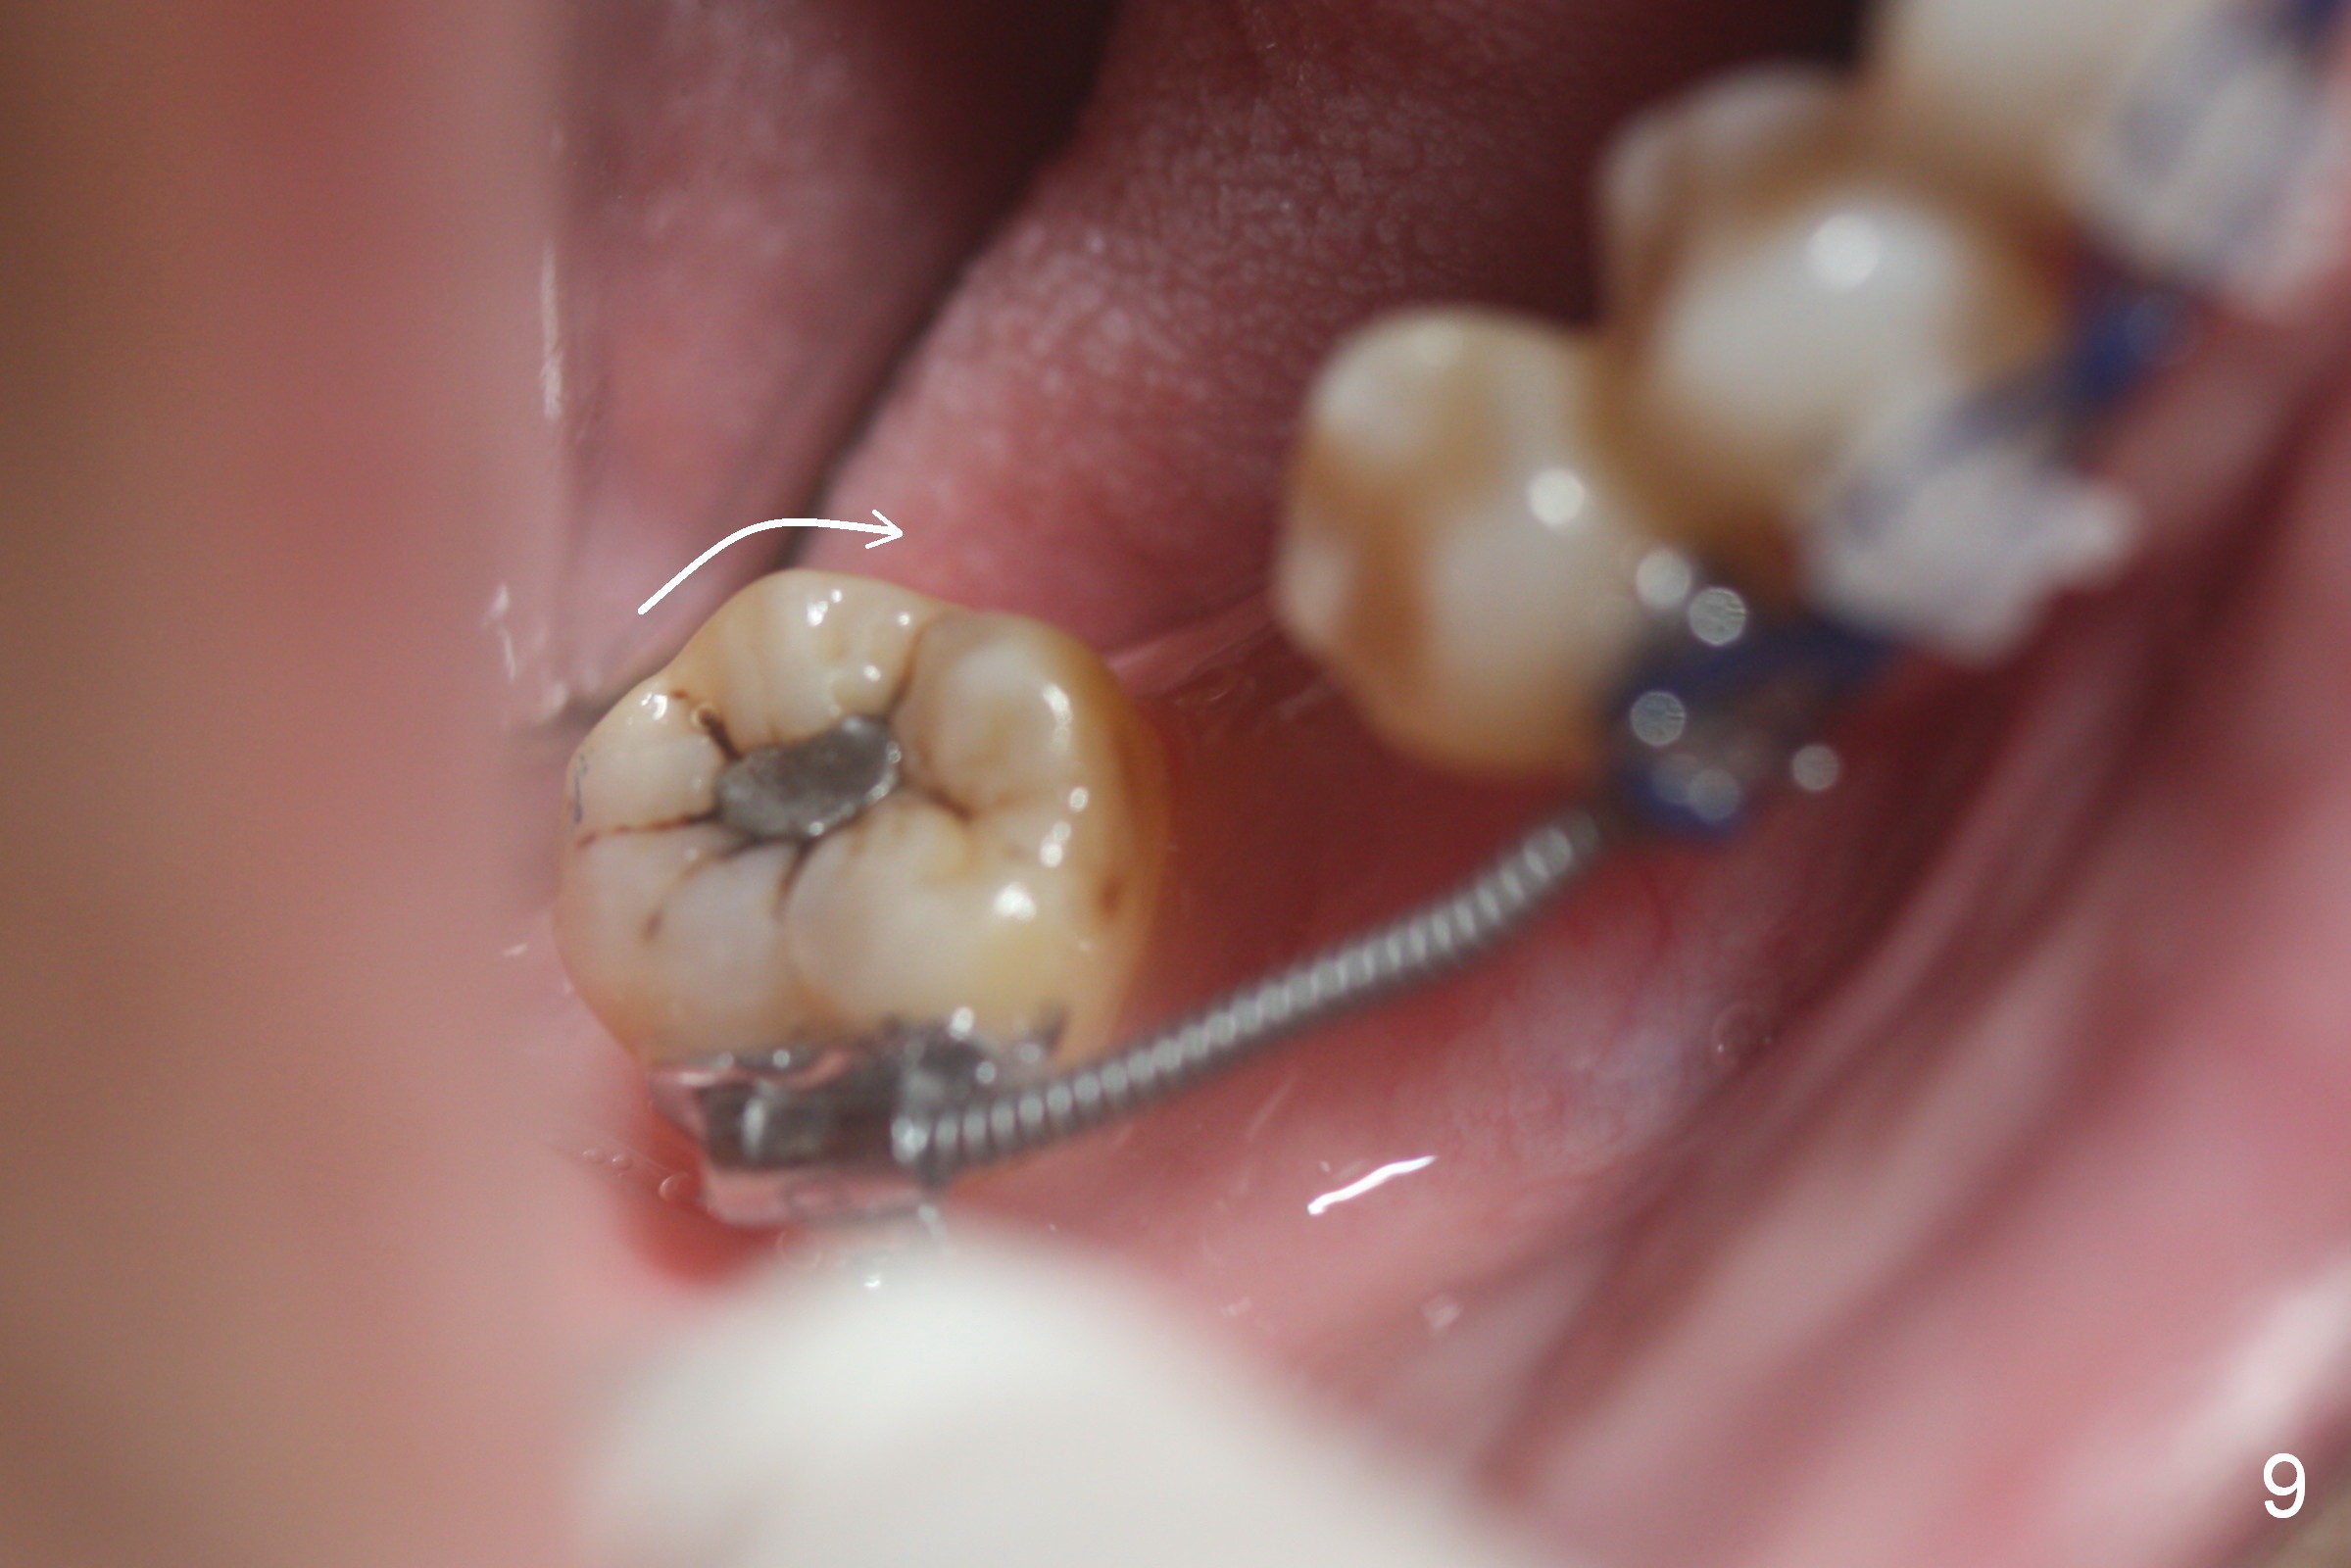

Four weeks of using open coil spring between #29 and 31, these teeth seem to have rotated (Fig.8,9 curved arrows). After placing a longer spring and the same arch wire, power chains are installed to close the anterior diastema (Fig.10 ^). The patient notes the divergence between #20 and 21 (Fig.11). To correct the latter, either place #20 bracket more distal (Fig.11 *) or place power chains between these teeth only. To facilitate #31 distalization (Fig.13), place lingual buttons (Fig.12 red) in the mesial surface of #31 and the distal of #2 with an elastic between the buttons.